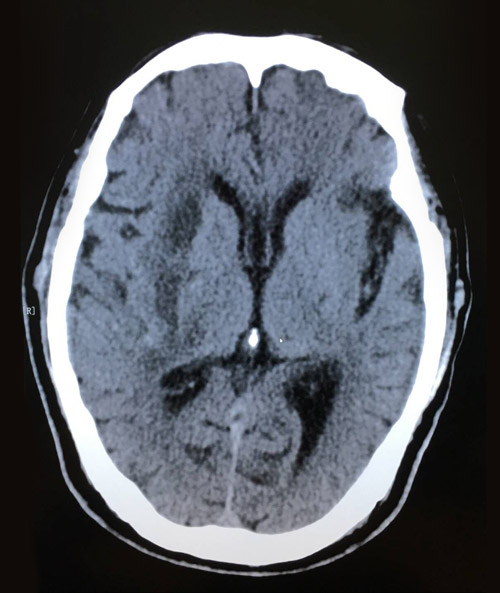

術(shù)后影像:腦出血引流術(shù)后,幾乎看不到血腫殘余

現(xiàn)在秦大爺已轉(zhuǎn)回普通病房,飲食,睡眠都恢復(fù)如常,肢體活動也在慢慢恢復(fù),再過不久就可出院了。